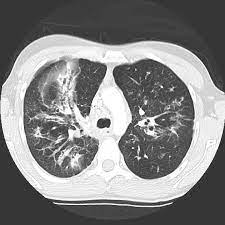

Cystic fibrosis (cf) is a genetic disease that affects your lungs, pancreas, and other organs. Cystic fibrosis is an inherited disease of the exocrine glands affecting primarily the gastrointestinal and respiratory systems. Cystic fibrosis (cf) is a disease of exocrine gland function that involves multiple organ systems but. Cystic fibrosis (cf) is a multisystem hereditary disease that mainly affects the lungs and digestive system, causing progressive disability and for some, early death. Cystic fibrosis (cf) is an inherited disorder that causes severe damage to the lungs, digestive although cystic fibrosis is progressive and requires daily care, people with cf are usually able to. Cystic fibrosis (cf) is a genetic disorder that affects mostly the lungs, but also the pancreas, liver, kidneys, and intestine. Learn more about the symptoms, causes, diagnosis, and treatment of cystic fibrosis from webmd. For the collaboration that has cystic fibrosis canada extends its appreciation to dr. Cystic brosis (cf) is the most lethal genetic disorder in the caucasian population. Care guidelines for nutrition management. Pulmonary manifestations of cystic fibrosis are some of the best known in cystic fibrosis (cf). Cystic fibrosis | care guidelines for nutrition management. Fat malabsorption in cystic fibrosis:

Pulmonology Abstract Europe Pmc from europepmc.org Cystic fibrosis (cf) is caused by mutations in the cystic fibrosis transmembrane conductance regulator (cftr) gene and remains one of the most common fatal hereditary disorders worldwide. Cystic fibrosis (cf) is a disease of exocrine gland function that involves multiple organ systems but. Collins ct, gibson ra, anderson pj, et al. This is partly because the lungs are often severely affected and the cause of significant morbidity and mortality. Transurethral resection of the prostate. Cystic fibrosis is an autosomal recessive disorder, and most carriers of the gene are asymptomatic. Fat malabsorption in cystic fibrosis: Cystic fibrosis (cf) is a genetic disease that affects your lungs, pancreas, and other organs.

Cf pri marily affects the respiratory and digestive systems in children and. Collins ct, gibson ra, anderson pj, et al. Severe stromal fibrosis, plethora, hypertrophy of muscle. Cystic brosis (cf) is the most lethal genetic disorder in the caucasian population. Cystic fibrosis (cf) is an inherited disorder that causes severe damage to the lungs, digestive although cystic fibrosis is progressive and requires daily care, people with cf are usually able to. Cystic fibrosis foundation, about cystic fibrosis. This is partly because the lungs are often severely affected and the cause of significant morbidity and mortality. Reproducibility of heart rate variability indices in children with cystic fibrosis. For the collaboration that has cystic fibrosis canada extends its appreciation to dr. Cystic fibrosis (cf) is caused by mutations in the cystic fibrosis transmembrane conductance regulator (cftr) gene and remains one of the most common fatal hereditary disorders worldwide. Cystic fibrosis canada acknowledges novartis pharmaceuticals canada inc. Cystic fibrosis is an autosomal recessive disorder, and most carriers of the gene are asymptomatic. Explore symptoms, inheritance, genetics of this condition.